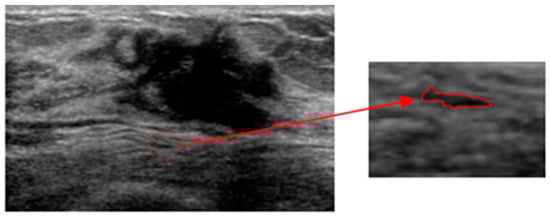

An Automatic Localization Algorithm for Ultrasound Breast Tumors Based on Human Visual Mechanism

Xie, Y.; Chen, K.; Lin, J. An Automatic Localization Algorithm for Ultrasound Breast Tumors Based on Human Visual Mechanism. Sensors 2017, 17, 1101. https://doi.org/10.3390/s17051101